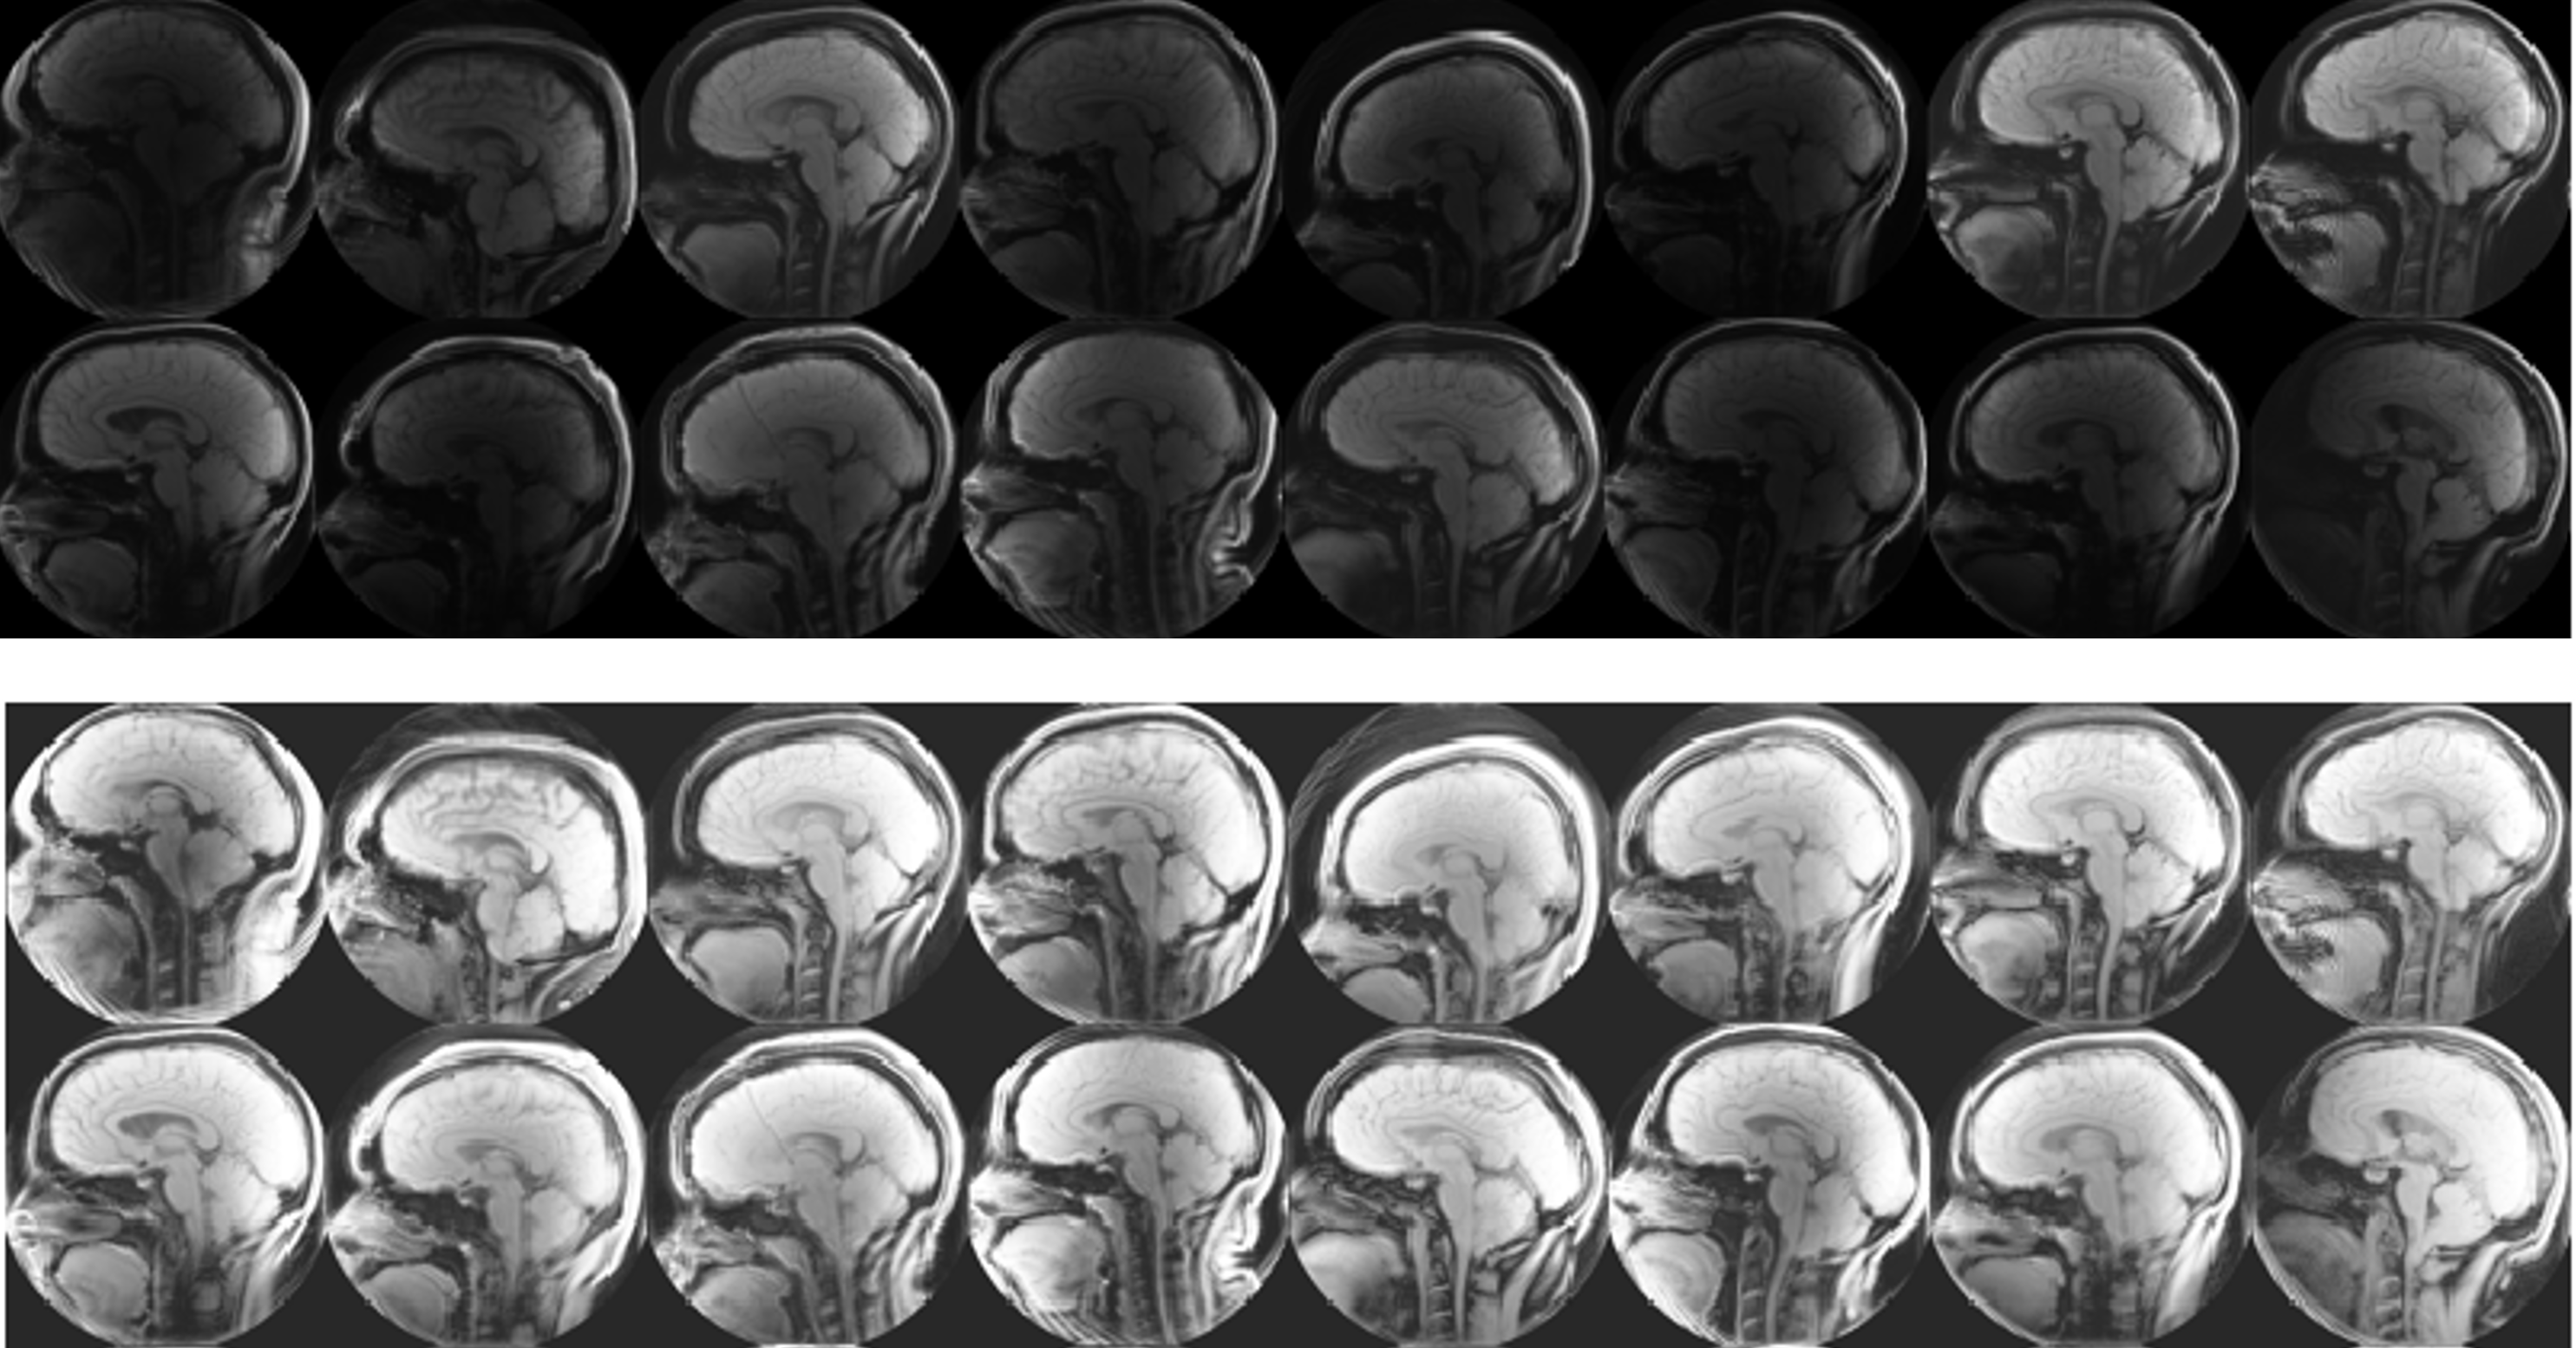

Since the brightness and contrast levels varied across the magnitude images in a way that made segmentation more difficult, we pre-processed the data using histogram normalization. To this end, we used the MATLAB function histeq, which approximately linerarizes the cumulative distribution function and helps create a more uniform set of images. Figure 3 compares a sample of original and normalized images. For more explanation of this process, see [5].